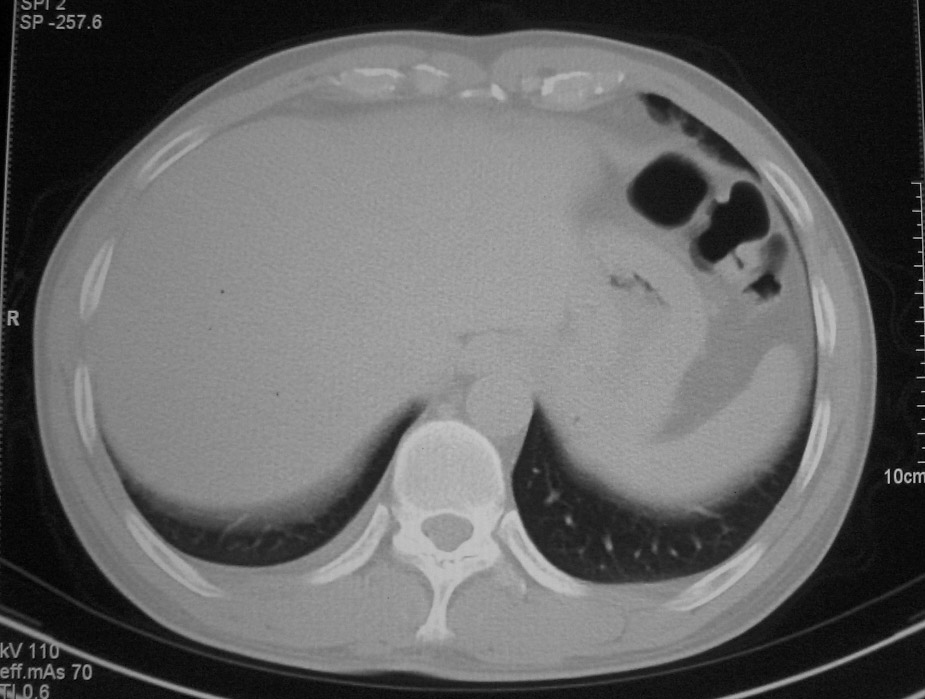

左肺上叶不张,左肺上叶支气管狭窄,呈鼠尾征,左侧胸腔内见少许积液,考虑左肺上叶中心型肺伴左侧胸腔内少许积液可能,不除外结核,建议支气管镜检查.

左肺上叶不张,左肺上叶支气管狭窄,呈鼠尾征,左侧胸腔内见少许积液。

考虑:1、左肺上叶中心型肺伴肺不张、左侧少量胸腔积液;

2、可疑纵隔淋巴转移;

3、建议支气管镜检查。

右上叶支气管肺癌并右上叶阻塞性不张,右侧少量胸腔积液.

右肺上叶中央型肺癌并上叶肺不张、纵隔淋巴结肿大.右侧少量胸腔积液。

右上肺中心型肺癌并肺不张,纵膈淋巴结肿大。右侧少量胸腔积液。

右肺上叶不张,考虑中央型肺癌。右侧胸膜肥厚